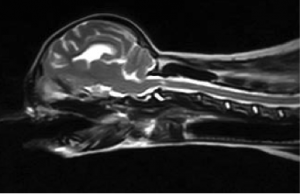

術前レントゲン

レントゲンより軸椎の背側棘突起と環椎間にて間隙があり、VD像にて歯突起の低形成が確認されました。MRIでも環軸椎間にて脊髄の高信号があり典型的な環軸椎亜脱臼症と判断されます。また、この症例では環椎の頭蓋内への陥入があり環椎後頭骨オーバーラッピングが存在すると思われました。人医療とは異なり動物に対する治療はまだわかっていないために環軸関節の固定のみを実施しました。